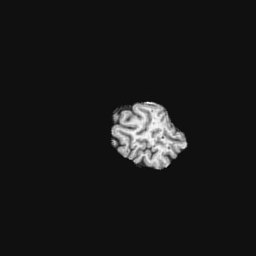

Exp. 2: Fetal brain data is used to test the robustness of our approach under real conditions. Fetuses younger than 30 weeks very often move a lot during examination. Fast MRI sequences allow artifact free acquisition of individual slices but motion between slices corrupts consistent 3D information. Fig. 3 shows that our method is able to accurately predict also under these conditions. For this experiment we use from three orthogonally overlapping stacks of ssFSE slices covering the fetal brain with approximately 20-30 slices each. We are ignoring the stack transformations relative to the scanner and treat each individually. For , 28 clinically approved motion compensated brain reconstructions are resampled into a volume with spacing. A density of 500 unique sampling normals has been chosen via the Fibonacci sphere sampling method with 25 sampling planes evenly spaced between -25 to +25 on the Z-axis. This gives a plane spacing of 2mm, sampling only the middle portion of the fetal brain. Training took approximately 10hrs for 30 epochs. Prediction, i.e., the forward pass through the network, takes approx. 12 ms/slice.

Slices, from a motion corrupted MRI stack, are segmented and cropped. Since there is no ground truth for the queried images, an arbitrary fetal atlas is used for visualization in Fig. 11 and 12.